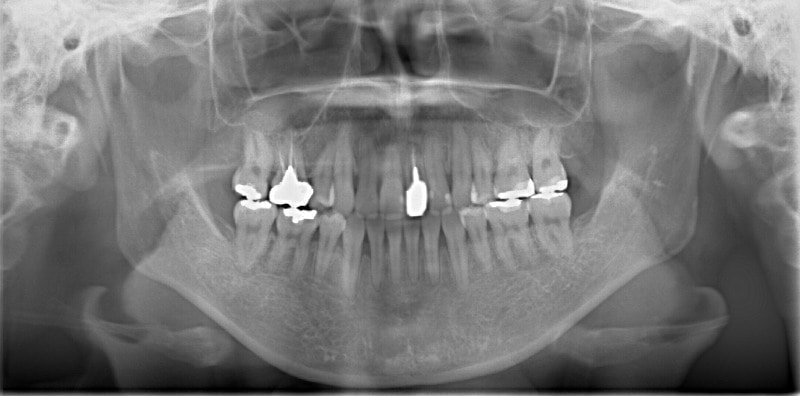

治療開始から約1年後

歯根のパラレリング(平行性)が獲得されております。

下顎8番は、両側抜歯済みです。

顎位は良好な状態です。